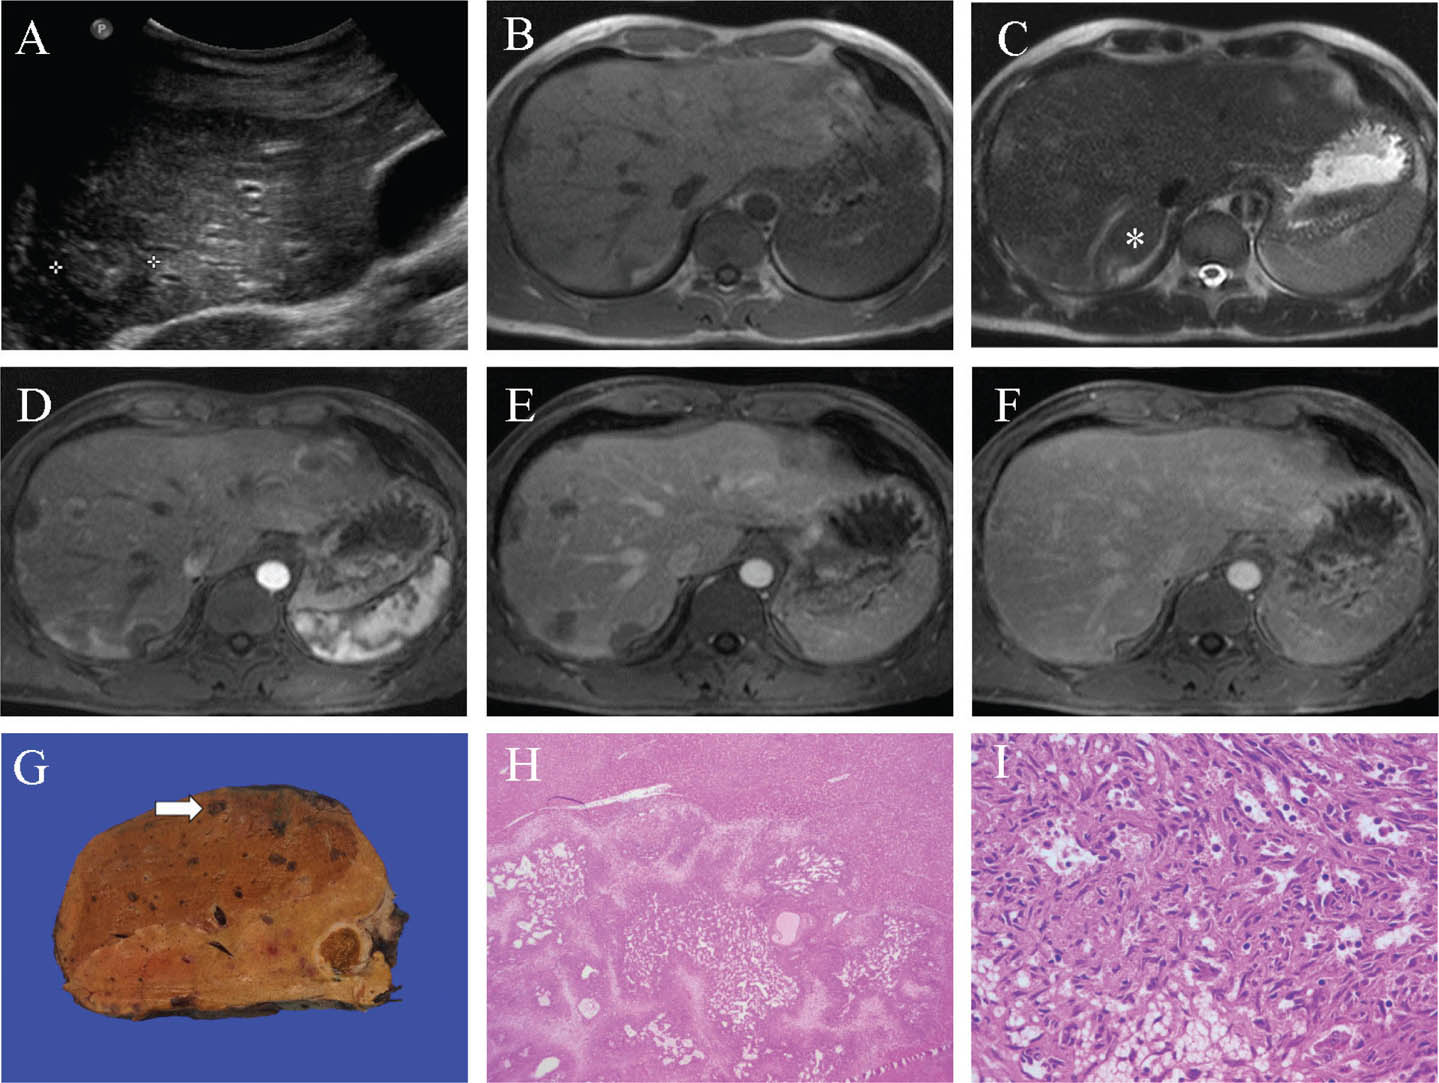

Fig 1

Figure 1. Representative images of focal nodular hyperplasia. A. On portal phase CT in liver windows the isoenhancing lesion with hypoenhancing central scar in segment 2/3 is subtly appreciated (white arrow to the edge of lesion), subtly bulging the inner contour of the left lobe, a so-called “stealth” lesion. B and C. On MRI in a different patient, a similarly located segment 2/3 lesion is isointense with the background liver on the T1 weighted image (B) and T2 weighted image (C). D and E. Following intravenous gadoxetic acid administration, the lesion shows homogenous hyperenhancement during the arterial (D) and portal (E) phases. F. On the hepatobiliary phase at 20 minutes, the lesion shows uniformly higher signal than the background liver. G and H. A partial hepatectomy from a separate patient shows a well-circumscribed lesion with a central stellate scar (white arrow) and radiating fibrous septae, seen grossly (G) and microscopically (H). I. Ductular reaction (black arrow) is present at the interface of fibrous regions with nodules. Slides are stained with Hematoxylin and Eosin. Total image magnification: H - 25X; I - 100X.

FNH can be subtle on unenhanced imaging, due to the benign hyperplastic tissue blending in with adjacent liver parenchyma, classically described as a “stealth lesion” (8). On ultrasound, the central scar may be indistinctly visualized; otherwise, FNH echogenicity is varied and nonspecific. However, contrast-enhanced ultrasound, CT, or MRI is usually diagnostic. The central feeding artery with centrifugal flow may be seen as the characteristic “spoke-wheel” pattern on color Doppler, CEUS, and sometimes CT arterial phase, most commonly in larger lesions (9). FNH is typically a subtle hypoattenuating or isoattenuating homogenous lesion on unenhanced CT. On multiphasic CT, the arterial phase is most diagnostic for FNH, with homogenous enhancement and hypoattenuating central scar, if present. On the portal-venous phase, enhancement is subdued, appearing mildly hyperattenuating or isoattenuating to the liver with the scar remaining hypoattenuating. On delayed phase imaging, the scar is typically hyperenhancing, with the remainder of the lesion isoattenuating.

MRI provides the most diagnostic characterization of FNH (with a specificity of 98%) (10). FNH is T1-weighted imaging (T1WI) isointense or slightly hypointense, and T2-weighted imaging (T2WI) isointense or slightly hyperintense. If present, the central scar is T1WI hypointense and T2WI hyperintense. Similar to CEUS and CT, during the arterial phase, FNH demonstrates intense homogenous enhancement (sparing the central scar), is relatively isointense on portal-venous phase (hypointense scar), and isointense on delayed phase (hyperintense scar). Gadoxetic acid-enhanced MRI is sensitive for FNH, showing a high signal on the hepatobiliary phase at 20 minutes, which aids in differentiation from other arterial enhancing liver lesions, such as adenomas (11).